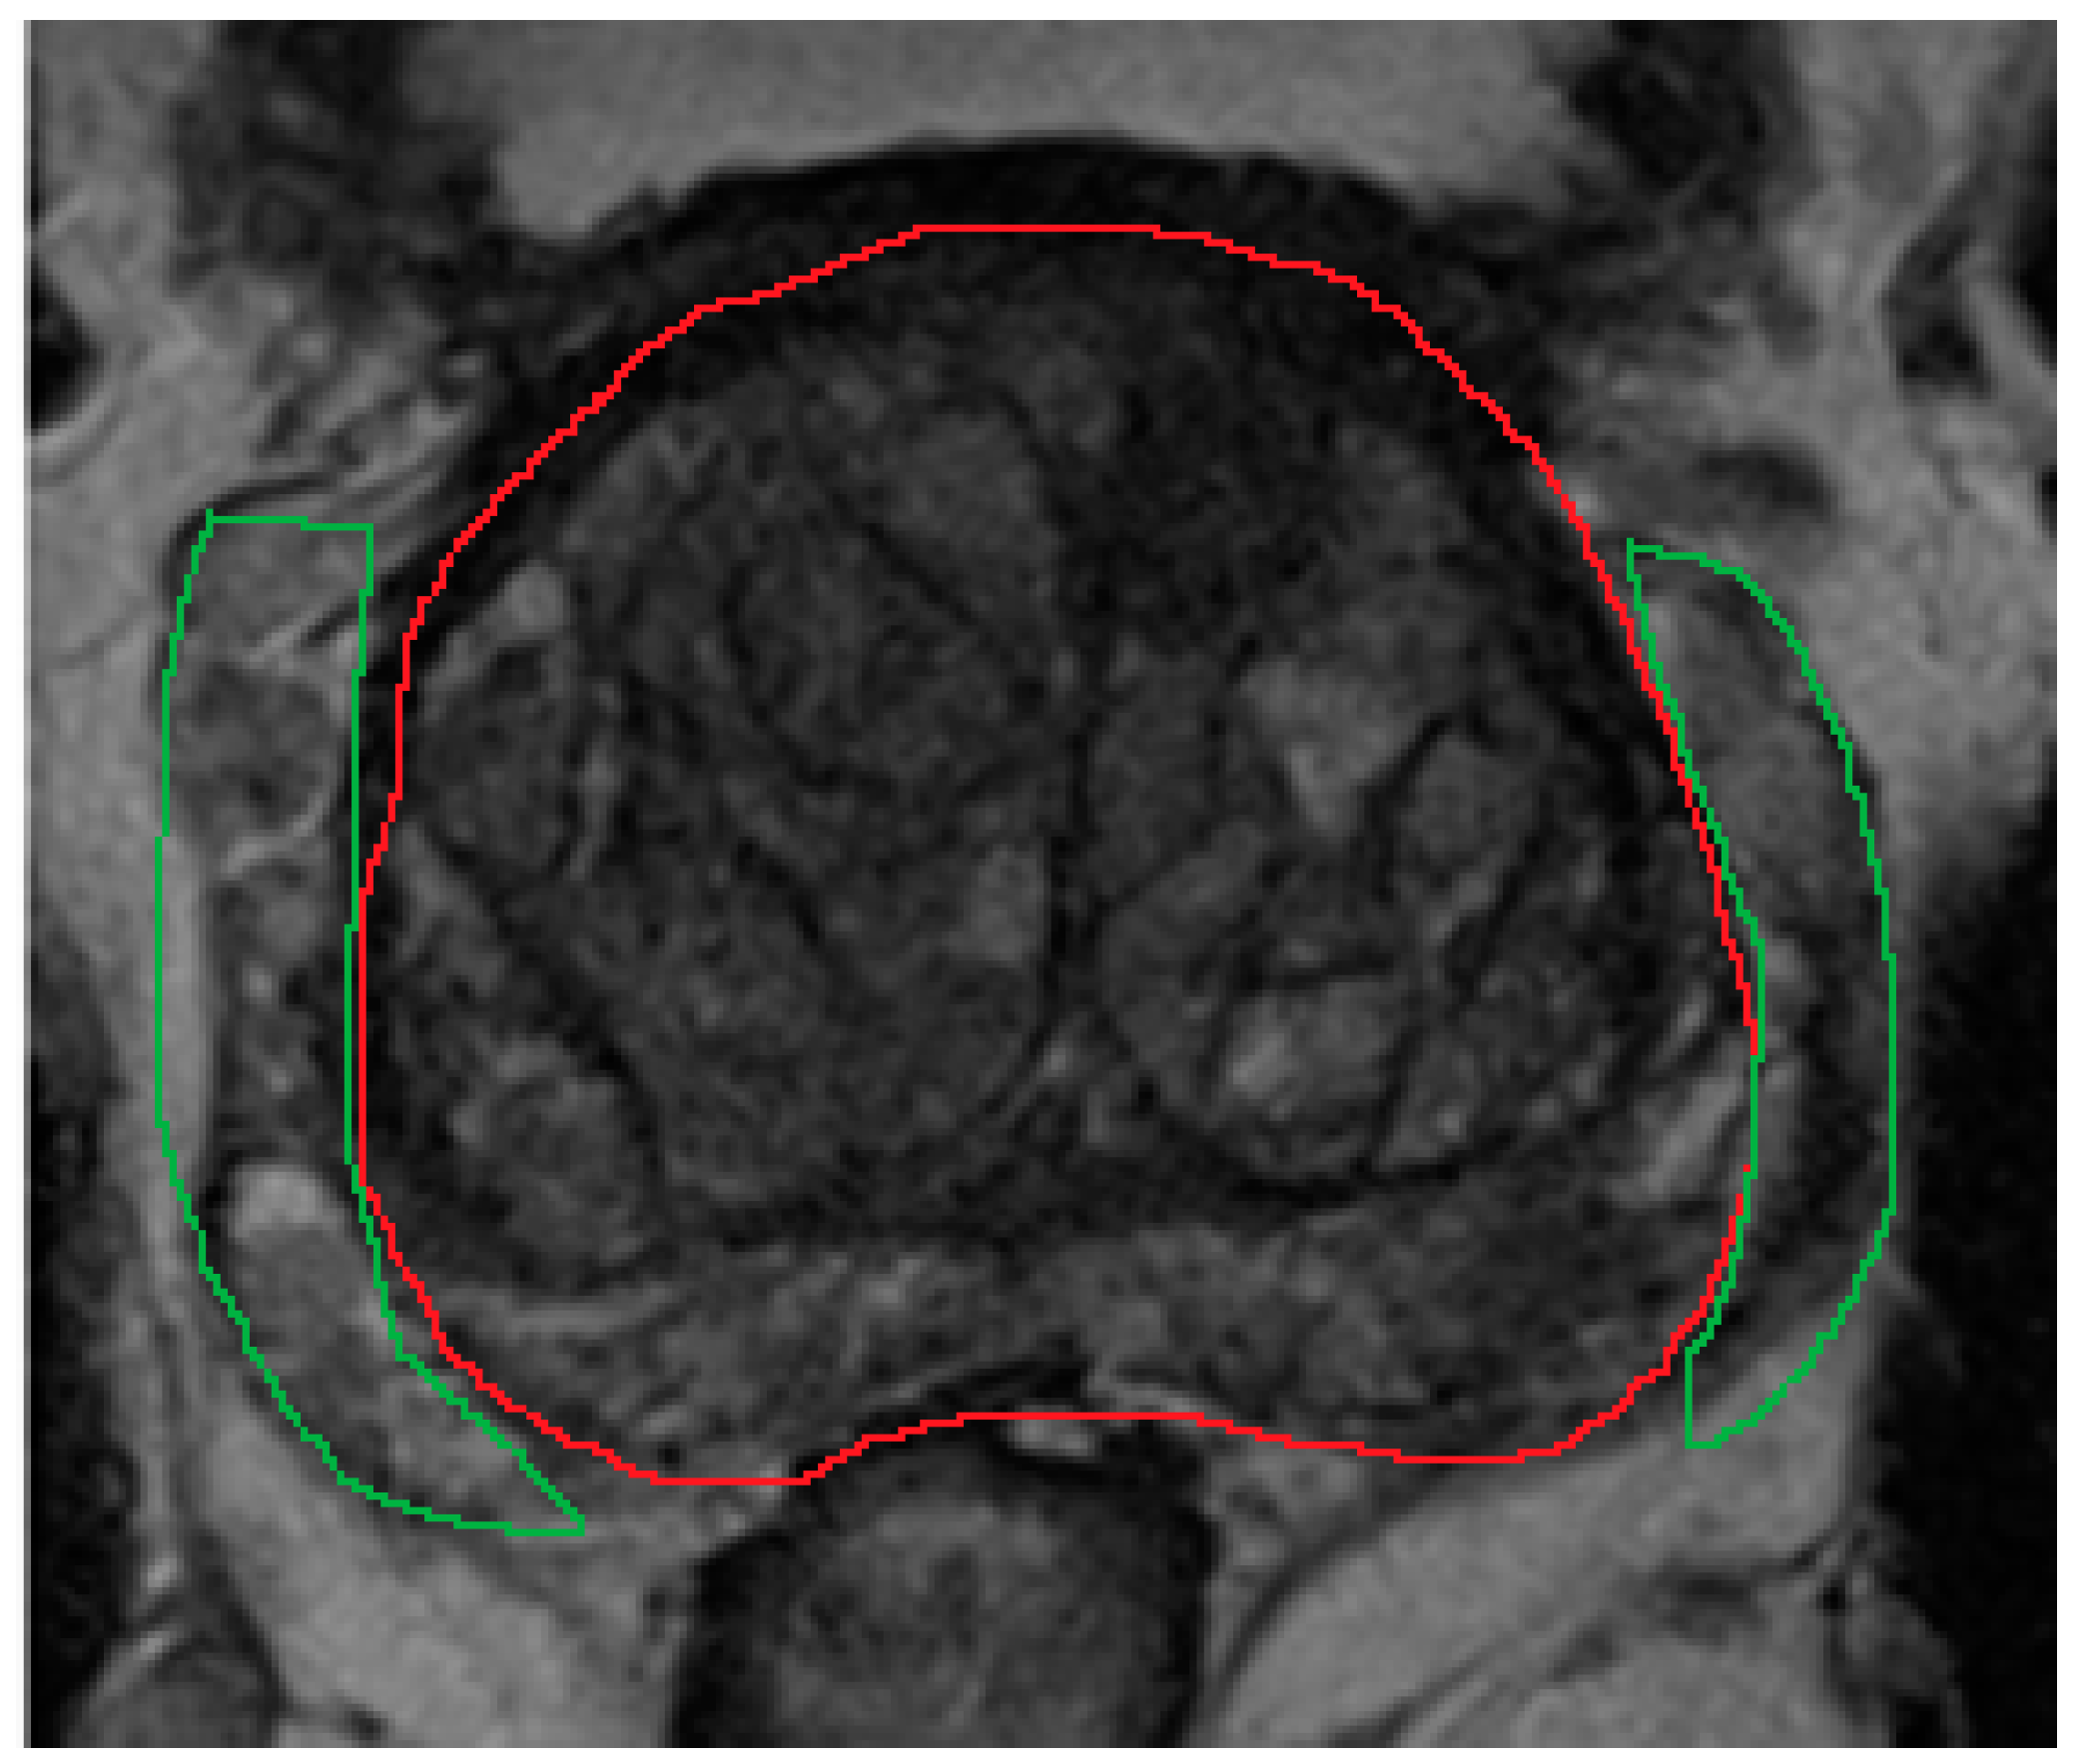

The aim of segmentation is to define the boundary of the prostate gland, prostate zones (central, transition, peripheral zones), and any focal lesions. Gland and lesion segmentation is important when performing fusion-based targeted biopsy or focal therapy, as these clinical settings require the accurate delineation of prostate, zonal, and lesion contours. Segmentation can be performed either manually or by ML/DL methods. In practice, manual segmentation can be time-consuming and subjective, depending on the experts’ perception and level of experience. This can range from highly accurate when delineating the transition zone from the peripheral zone, to highly subjective and variable when delineating the prostate margins from periprostatic venous plexus in the mid-gland to apex regions (Figure 1).

Figure 1.

On MRI, the periprostatic venous plexus appears as serpinginous hyperintense structures with foci of signal voids adjacent to the prostate (green outline), and can be closely related to the prostate capsule (red outline). It may have similar heterogeneous appearance as the peripheral zone. Therefore, during manual segmentation, it can be mistaken as part of the prostate to less experienced operators.